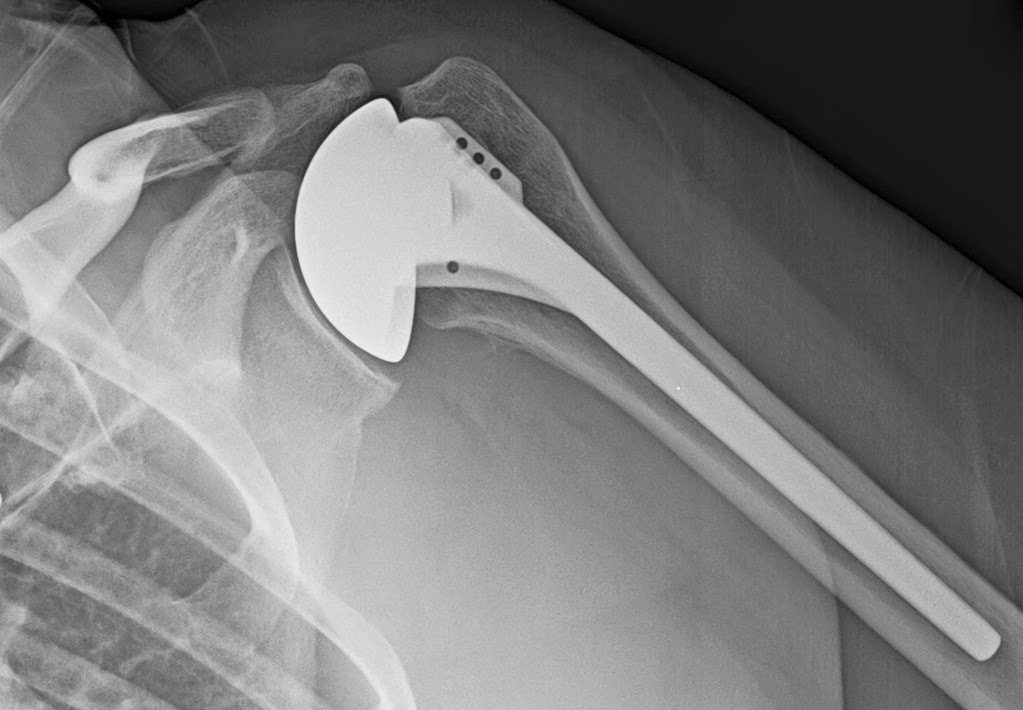

Arthrex Eclipse™ Stemless Shoulder Arthroplasty System

Arthrex Eclipse™ Stemless Shoulder Arthroplasty System Shoulder Arthroplasty X Ray in this article, we review the preoperative imaging features used for planning shoulder. hhra and stemless shoulder arthroplasty are used to treat isolated humeral head abnormalities, such as. the most common indications for shoulder arthroplasty are osteoarthritis,. mri is best for evaluating soft tissue structures and evaluating bone contusions or trabelcular microfractures. Shoulder Arthroplasty X Ray.